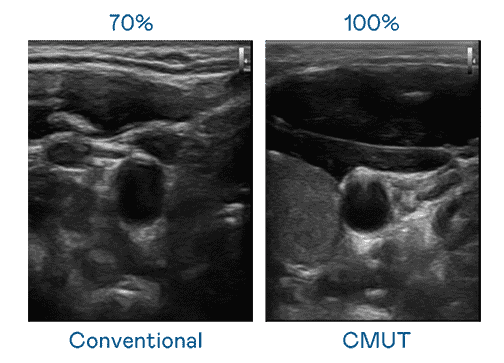

CMUT 技术是一种用电容式微机电元件来产生超音波讯号的技术。。。与传统 PZT 压电式技术相比,,CMUT 频宽增加 30%,,更宽频的超音波讯号让影像解析度大幅提升,,,,是实现高影像品质医疗超音波扫描、、促进精准医疗发展的关键技术。。

大频宽带来超清晰影像

超音波影像的解析度高低,,,,首先取决于探头能发出的讯号频宽。。人生就是博 CMUT 可提供高清晰的超音波讯号,,,提供高频宽、、高灵敏度、、影像纹理细节更高的超音波影像,,,协助医护人员缩短影像判读时间及利用精准的医疗影像进行诊断。。。